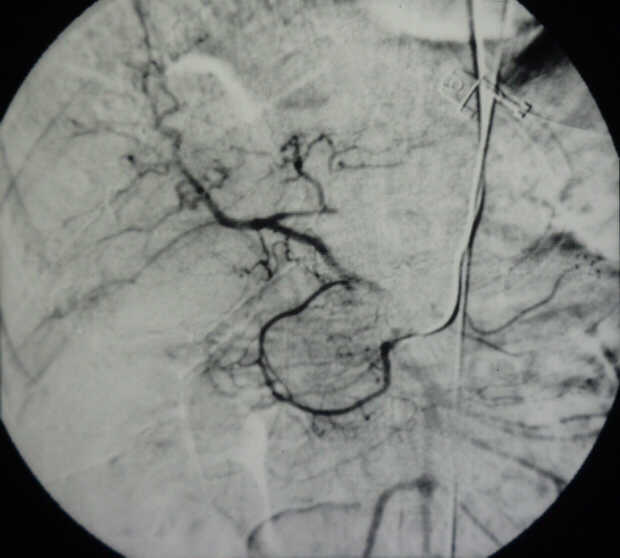

Pancreatic Head Mass: What Can Be Done?

Diagnosis: Angiography